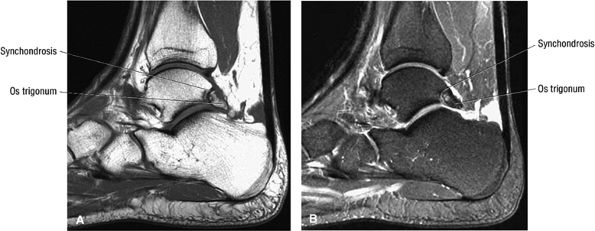

FIGURE 5.25 ● Sagittal anatomy of the ankle and foot. (A) The origins of the anterior talofibular ligament and posterior talofibular ligament are identified arising from the anterior and posterior distal tip of the lateral malleolus. From the origin, the full course of these ligaments can be followed medially on successive sagittal images to their insertions on the anterior and posterior talus. (B) The vertical course of a long segment of the peroneus longus and brevis tendons is often visualized on a single sagittal image through the tendons. This image is useful to further characterize tendinosis and longitudinal tears or splits, and for measuring the gap between completely ruptured tendon fragments. (C) The anterior process of the calcaneus is a common location for fractures that are occult on plain film. They are optimally visualized in the sagittal plane on MR exams. (D) In addition to occurring at the tibiotalar joint, degenerative arthrosis is also commonly found at the posterior subtalar, calcaneocuboid, and talonavicular joints. The cartilage surfaces and subchondral bone at these articulations are optimally visualized in the sagittal plane. (E) The presence of an os trigonum posterior to the talus predisposes certain athletes with a predilection for plantarflexion to the os trigonum syndrome. This is diagnosed on sagittal MR images when edema is visualized within the os trigonum and extends across the synchondrosis into the posterior talus. (F) Abnormal signal in the sinus tarsi manifests as high signal on FS fluid-weighted sequences and low signal on non-FS sequences. This abnormal signal may suggest, but is not specific for, inflammation in the sinus tarsi. Other causes of abnormal signal in the sinus tarsi, which may be incidental and asymptomatic, include extension of joint fluid from the posterior and middle subtalar joints, extension of generalized edema throughout the soft tissues of the ankle from stasis or other causes, enlarged vessels, and ganglion cysts.(G) Two potential causes of an incidental “mass” palpated on physical examination about the Achilles tendon are a low-lying soleus muscle and an accessory soleus muscle, both of which are diagnosed by MR imaging. The normal soleus muscle extends to about the proximal one third or one half of the Achilles tendon. A low-lying soleus will extend to the distal third of the tendon. An accessory soleus is present when there is an extra muscle in the pre-Achilles fat, usually extending to the distal third of the tendon, often near the distal insertion. (H) In the setting of a complete Achilles tendon rupture, the location of the tear may be at the myotendinous junction, mid-tendon, distal tendon, or tendon insertion at the os calcis. In addition, the tear is characterized as transverse or oblique longitudinal. In the case of transverse tears, the distance between the tear and tendinous insertion at the calcaneus is measured. Also, the length of good-quality tendon stump at the calcaneal insertion is measured, since the surgeon often uses the distal stump in the surgical reconstruction or repair. (I) The anteromedial aspect of the tibiotalar joint is a common location for the formation of large osteophytes, which extend anteriorly from the anteromedial tibia and talus. These may cause pain, limit the range of motion, or break off and form loose bodies within the tibiotalar joint. This spectrum of findings is part of the anteromedial impingement syndrome. (J) Ancillary findings at the plantar aponeurosis visualized on sagittal images include bone marrow edema within the inferior calcaneus, inferior calcaneal enthesophyte with marrow edema, and high signal within the flexor digitorum brevis muscle and fat that surround the plantar aponeurosis. These findings suggest active inflammation in the tissues surrounding the plantar aponeurosis. (K) The deltoid ligament is found on sagittal images by finding its origin extending off the bilobed medial malleolus. The medial course of the deltoid ligament components is followed over the next two or three successive sagittal images. (L) The vertical course of the tibialis posterior tendon and the flexor digitorum longus tendon is often visualized on a single image. Triangulating on tendon pathology in both the sagittal and axial planes aids in further characterizing tendon abnormalities.

hyperintensity on T1-weighted images, secondary to fatty marrow. This finding should not be mistaken for tendon degeneration or a tear. Accessory bones, including the os tibiale externum (an accessory navicular bone medial to the navicular) and the os trigonum (located posterior to the talus and occurring approximately 10% of the time), represent commonly seen secondary ossification centers. These are normal variants that may be misinterpreted as a fracture or loose body.21